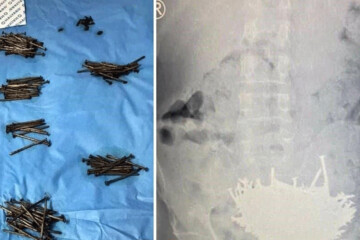

ببینید | خارج کردن ۲۳۰ میخ و قطع شیشه از شکم یک بیمار

پزشکان ۲۳۰ میخ و قطعات شیشه از شکم یک بیمار در عربستان خارج کردند. منبع: مشرق نیوز